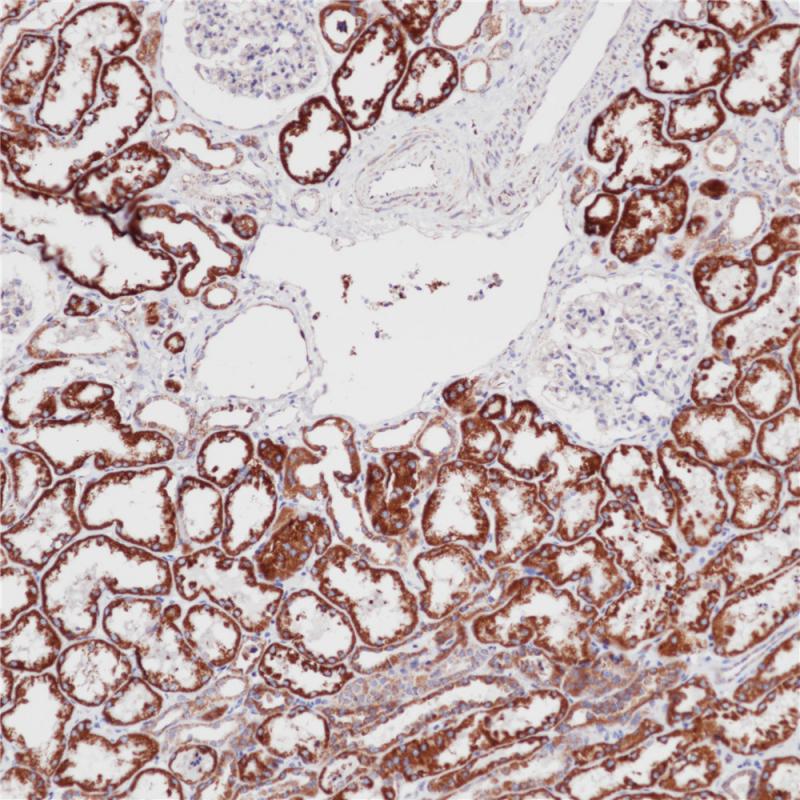

N-Cadherin 重组兔单克隆抗体

N-Cadherin(神经型钙粘蛋白)是钙粘蛋白家族的一员,能够与钙离子结合并介导细胞间粘附。经典型钙粘蛋白包括E-Cad(上皮型钙粘蛋白)、N-Cad和P-Cad(胎盘型钙粘蛋白)等。经典型钙粘蛋白的特征性结构为胞外区含5个能够钙离子结合的重复区,另外还包括跨膜区和一个序列保守的胞内区。胞内区通过与链蛋白(Catenins)结合介导钙粘蛋白分子与细胞内骨架成分相连。N-Cadherin可表达在多种细胞类型中,包括神经、心肌和间质性细胞中。

细胞膜,细胞质